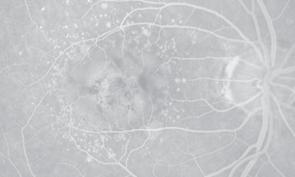

Foveální avaskulární zóna (FAZ) se nachází uvnitř fovey, ale svou velikostí přesahuje hranice foveoly. Její rozsah je variabilní (250–600 μm) a přesnou lokalizaci můžeme detekovat pouze pomocí fluorescenční angiografie. Sítnice zde neobsahuje retinální

kapilární cévní systém, a proto je její výživa zcela závislá pouze na difuzi z okolních okrsků sítnice a choriokapilaris . Avaskulární zóna fovey je obklopena cévními arkádami – cirkulárním systémem kapilár ve vnitřní jádrové vrstvě (centrální kapilární prstenec) – viz obr. 1.2 a 1.4 – a umožňuje přístup světla k fotoreceptorům foveoly, aniž by při průchodu sítnicí interferovalo s jakoukoliv cévou.

Obr. 1.4 Foveální avaskulární zóna, detail foveální oblasti na snímku fluorescenční angiografie